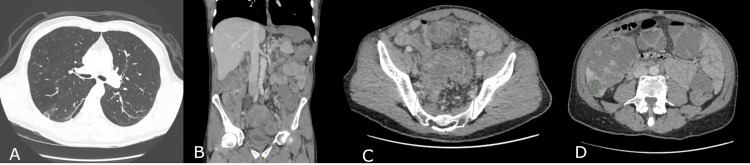

再次复查胸部、腹部及盆腔CT(图4)显示乙状结肠长段肠壁增厚伴管腔狭窄,区域淋巴结肿大,肝脏多发转移灶,最大直径3.2 cm,右肺上叶见一6 mm可疑小结节。原发肿瘤与膀胱及左侧盆壁分界不清,提示局部侵犯可能。

图4. CT 成像,(A)轴位 CT 切片显示肺部病变,(B)冠状位 CT 切片显示乙状结肠肿块,(C)轴位切片显示乙状结肠肿块,(D)轴位切片显示肝转移